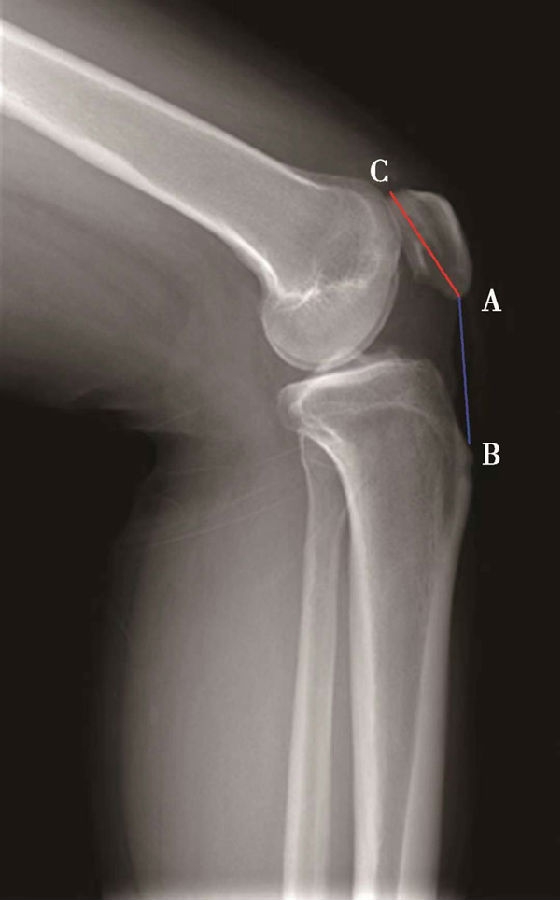

(3)BlackBurne-Peel指数>1.0提示高位髌骨(图8),<0.5提示低位髌骨(图9)。

体位:侧卧位,屈膝无要求。

如图示:AB是髌骨关节面最低点到胫骨平台延长线的垂直距离。AC是髌骨关节面的长度。BlackBurne-Peel指数=AB/AC(图7)。

图8 BlackBurne-Peel指数=AB/AC=1.20,为高位髌骨